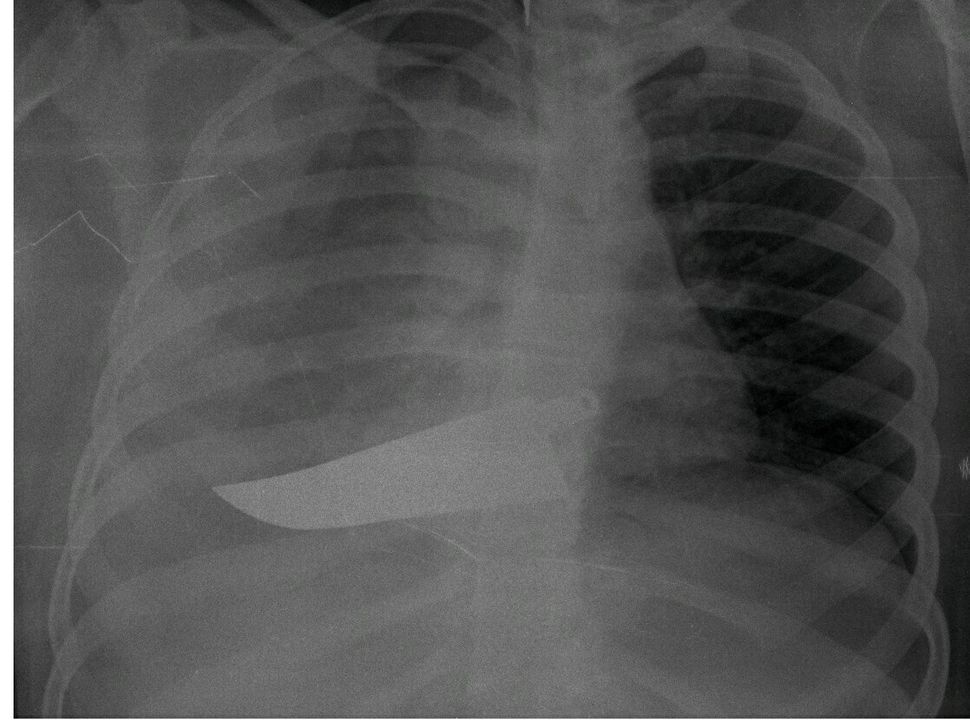

Questa è la storia di una delle protagoniste della mostra “L’invisibilità non è un superpotere”, all’Ospedale San Carlo di Milano dal 21 novembre all′8 dicembre 2019 che, attraverso fotografie e radiografie anonime, racconta il dramma delle donne arrivate nei Pronto Soccorso dichiarando di aver subito violenze, organizzata dall’ASST Santi Paolo e Carlo di Milano e Fondazione Pangea Onlus.

Tra le immagini, oltre alle ossa rotte, si vede un coltello piantato nella schiena.